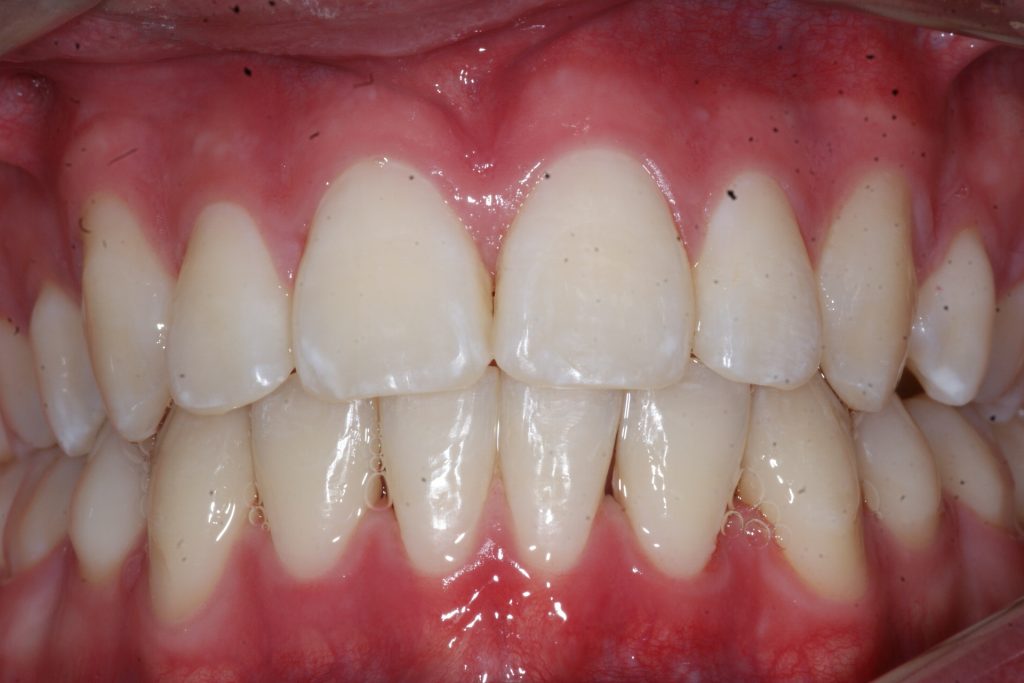

Correction d’une malocclusion de type bimax, canine #33 ectopique et chevauchement léger aux 2 arcades.  Des appareils fixes (broches) et extraction de 4 prémolaires furent nécessaires pour améliorer ce sourire.  Traitement chez un jeune adulte, réalisé en 28 mois.